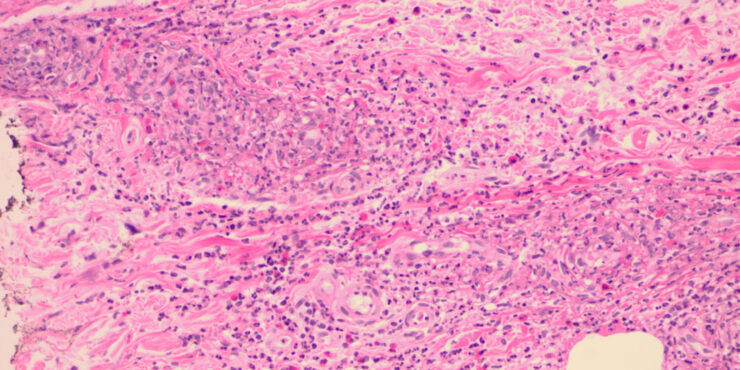

Hailey Hailey disease= ุงูููุงุน ุงูุนุงุฆูู ุงูุณููู ูููู ูููู HaileyHailey Disease Familial benign pemphigus is inherited as an autosomal dominant trait, with a family history obtainable in about two thirds of patients. Genetic studies have localized the key mutations to the ATP2C1 gene on chromosome 3q , specifically 3q21-q24, the area responsible for ATP-dependent calcium transport […]